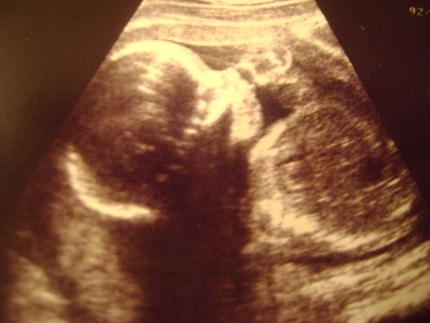

Плод на данном этапе развития достигает веса 400 граммов и длины около 20 сантиметров. У мальчиков в это время начинается процесс опускания яичек в мошонку, а у девочек уже образуются первичные яйцеклетки. На ультразвуковом исследовании можно заметить, как малыш зевает. У него уже формируется режим дня, схожий с режимом новорожденного.